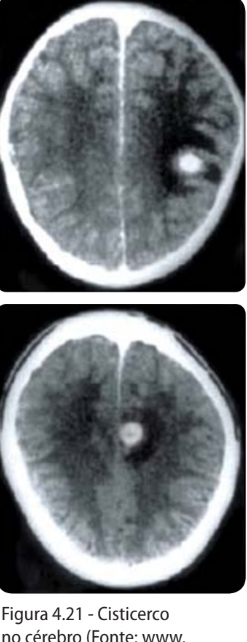

Quando o cisticerco se aloja no SNC, causa a […]

Neurocisticercose

NB: maioria assintomático, mas o cisticerco pode bloquear a drenagem de LCR nos ventrículos, causando hipertensão intracraniana.

O diagnóstico de cisticercose é realizado por exames de […]

Exames de imagem: TC, RM